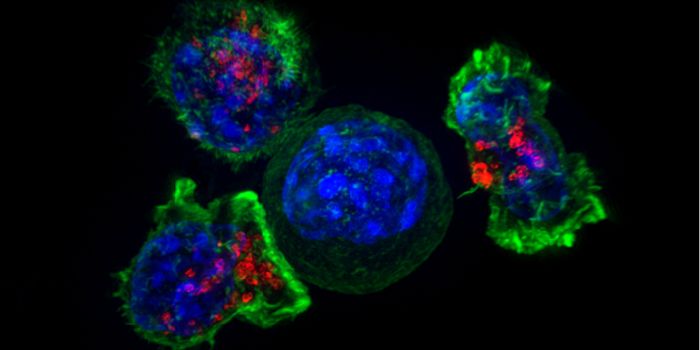

NOV 30, 2023CancerCytotoxic T cells (CTLs), a type of immune cells integral to fighting cancer, rely heavily on interaction with a molecul ...

SEP 19, 2023CancerNatural killer (NK) cells represent an important class of immune cells involved in anti-tumor immunity. Once ident ...